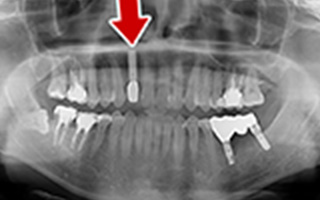

Before

After

| 45歳 男性 | 医療関係者紹介 |

|---|---|

| 主訴 | 右前歯が取れた(右上2) |

| 処置内容 |

1本インプラント埋入+再生療法 抜歯即時埋入⇒抜歯を行い、同時にインプラント埋入(即時埋入) |

| 治療費用 | 上顎: 約40万円(税込) |

| 治療期間 | 約11ヶ月 |

| リスク | 上部構造物、仮歯の破折、術後の腫れ(3日)、人工歯根脱落リスクがあります |